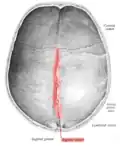

Sagittal suture seen from inside.